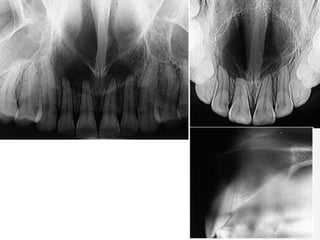

Incisive Canal Cyst

Incisive Canal Cyst Derived from epithelial remnants of the nasopalatine

Incisive Canal CystDerived from epithelial remnants of the nasopalatine duct (incisive canal)  4th to 6th decades  Palatal swelling common, asymptomatic  Radiographic findings  Well-delineated oval radiolucency between maxillary incisors, root resorption occasional  Histology  Cyst lined by stratified squamous or respiratory epithelium or both

Incisive Canal Cyst Treatment consists of surgical enucleation or periodic radiographs  Progressive enlargement requires surgical intervention